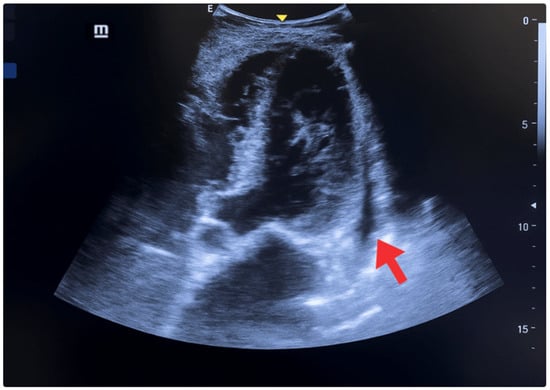

| 5 May | Acute episode of oppressive retrosternal chest pain (30 min, 8/10), with sudden moderate dyspnea, nausea, and profuse diaphoresis. He presented to the primary emergency department. Initial evaluation: BP 160/85 mmHg, SatO2 85%, signs of pulmonary and peripheral congestion. | -ECG: Biphasic T waves were present in the anteroseptal leads (V2–V4), consistent with a type A Wellens pattern. -Laboratory: elevated troponin I (0.16 ng/mL), (reference < 0.03 ng/mL). | POCUS: Ejection fraction of 40% (moderate systolic dysfunction), shortening fraction of 18%, EPSS of 10 mm, lateral wall hypokinesia, eccentric remodeling with ventricular dilatation, thickened interventricular septum, and a small non-circumferential pericardial effusion. At the lung level, diffuse B lines (50–60% of lung fields) were present, a pattern consistent with alveolar-interstitial syndrome of cardiogenic origin. | Initial treatment: oxygen, IV nitroglycerin, ASA 300 mg PO, clopidogrel 300 mg PO, rosuvastatin 40 mg PO, IV furosemide. |

| 6–7 May | Mild retrosternal chest pain, absence of dyspnea, and improved ventilatory mechanics. | ECG: Biphasic T waves were present in the anteroseptal leads (V2–V4), consistent with a type A Wellens pattern. | POCUS: Decreased pulmonary B lines in both lung fields (40–50%). | Referral to a more complex center. Enoxaparin 80 mg SC every 12 h is added. |

| 9–11 May | Hospital stay in an intermediate care unit. | ECG: -Rhythm: sinus (positive P wave in L1, L2, and aVF; each P wave is followed by a QRS complex). -Heart rate: 80 beats per minute. -Electrical axis: between (−60° left axis deviation). -P wave: duration ≤ 120 ms, amplitude ≤ 2.5 mm in limb leads. PR interval: 160 ms. -QRS complex: duration ≤ 110 ms. -ST segment: isoelectric. -T wave: positive in most leads, except aVR and V1. -Corrected QT interval (QTc): 400 ms. -Findings of left ventricular hypertrophy. | POCUS: -Absence of pulmonary and cardiac congestion. -Regular pleura, without thickening. -Marked reduction in B lines (<20%) in affected lung fields. -Reappearance of predominant A lines. -Absence of consolidation. Findings compatible with resolution of cardiogenic alveolar-interstitial syndrome after depleting therapy. -Ejection fraction (Simpson): 50–55% -EPSS: 7 mm (previously 10 mm). -Shortening fraction: 25%. -Less evident lateral hypokinesia. -Left chambers with reduced diameter and indexed end-diastolic volume (≤70 mL/m2). -Mild, stable, non-progressive pericardial effusion. | - |